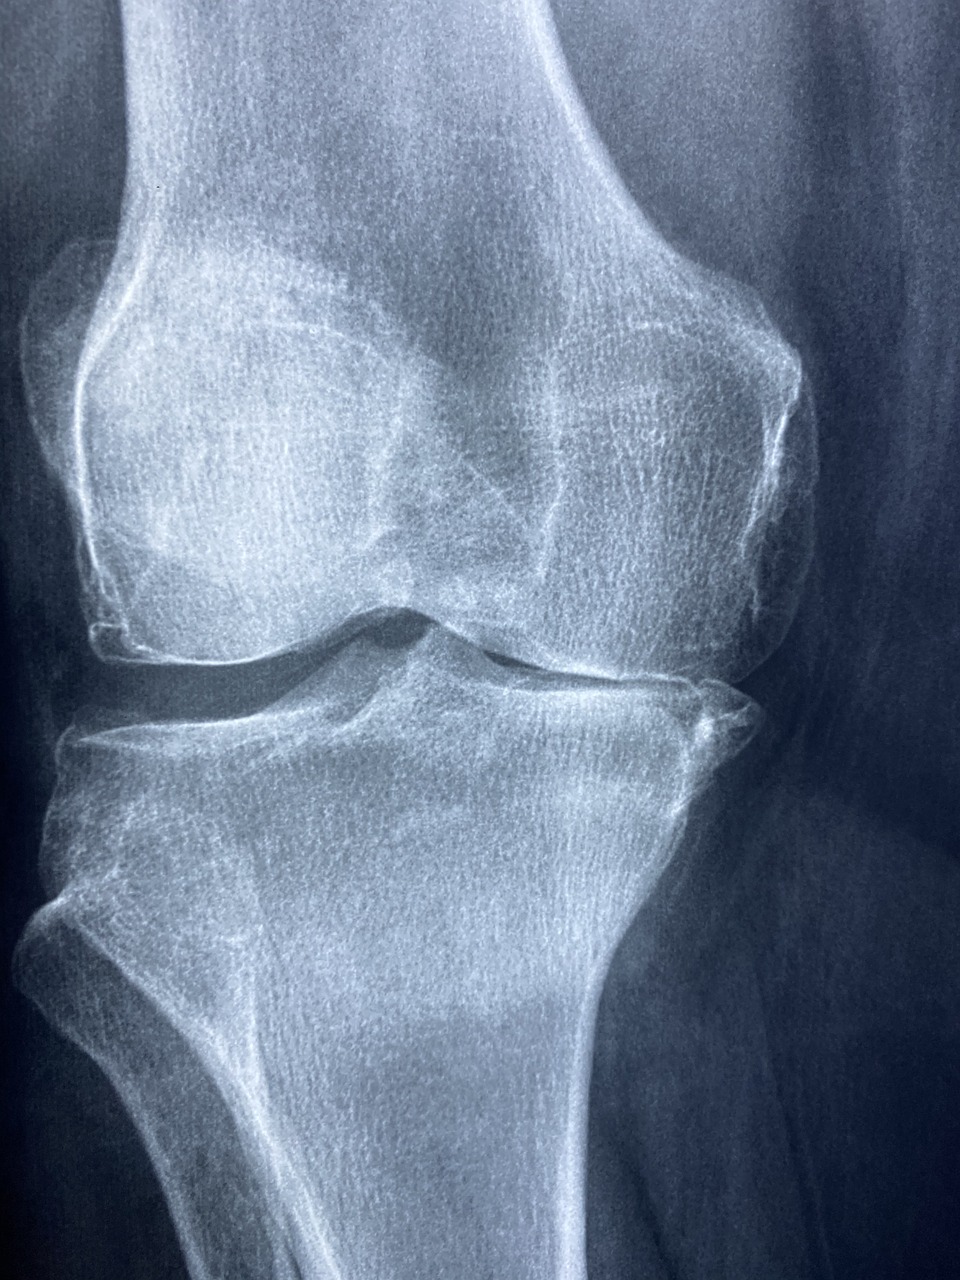

계단 오를 때 찌릿, 앉았다 일어나면 욱신…

이런 무릎 통증, 단순한 노화가 아니라 퇴행성 관절염의 시작일 수 있습니다.

퇴행성 관절염, 50대 이후 누구나 겪을 수 있습니다

- 관절을 덮고 있던 연골이 닳고 얇아지면서 통증 발생

- 주로 무릎, 손가락, 고관절, 척추 관절에 나타남